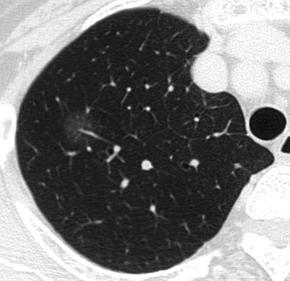

朋友們在行肺部CT檢查時,有時會發(fā)現(xiàn)一些小結(jié)節(jié),往往會緊張得不行。最主要是擔心這些小結(jié)節(jié)會不會是早期肺癌。一般來說,直徑小于1厘米的結(jié)節(jié)癌變的可能性比較小。但是這時小結(jié)節(jié)的形態(tài)、大小、周圍比鄰關(guān)系等等,與是否癌變的關(guān)系比較大。其中,比較重要的是一種叫做磨玻璃樣肺部結(jié)節(jié)的形態(tài)。肺磨玻璃樣結(jié)節(jié)(G)是磨玻璃樣改變的簡稱。在肺部CT影像上表現(xiàn)為密度輕微增加,增加程度小于實性改變,呈模糊的云霧狀,并可見其內(nèi)血管和支氣管紋理。

根據(jù)肺部磨玻璃影內(nèi)部成分均一程度的不同,G又可分為單純磨玻璃影(pG)及混合型磨玻璃影(mG)。G病變的鑒別范圍包括感染性病變、腫瘤等多方面。由于早期腫瘤也可表現(xiàn)為G,因此針對G病變予以單純手術(shù)切除后,可以達到腫瘤長期治愈的效果,5年生存率幾乎100%。而且,如果病理分期為I期的話,還免去了術(shù)后輔助治療。因此,在臨床上加強對于G病變的隨訪是有重要意義的。既然判斷G良惡性這么重要,我們該如何采取隨訪呢?